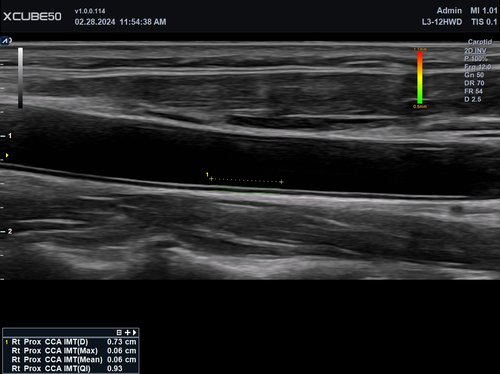

• L3-12H WD (3-12 MHz) für Ultraschalluntersuchungen in den Bereichen Gefäße, Weichteile, Bewegungsapparat (MSK), Pädiatrie